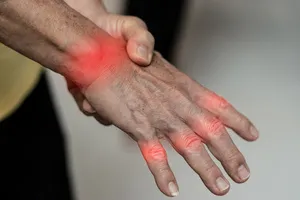

1. 통증

손가락 끝 마디, 중간 마디, 뿌리 마디 등 특정 부위 또는 전체 관절에 통증이 나타날 수 있습니다. 아침에 일어났을 때 가장 심하고, 활동하면서 점차 완화되는 경우가 많습니다.

2. 부종

관절 주변뿐만 아니라 손 전체가 부어 보일 수 있습니다. 가벼운 붓기부터 손가락이 굵어져 보일 정도의 심한 붓기까지 다양합니다. 붉게 변하거나 창백해질 수 있습니다.